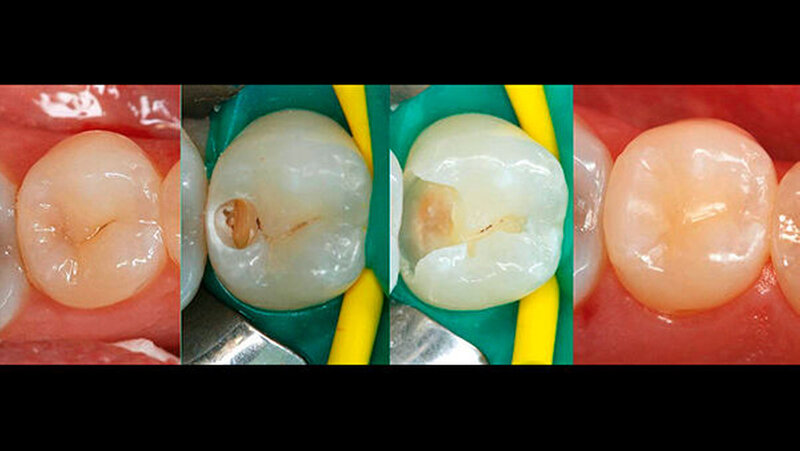

Bisher sind wir in der Ausbildung davon ausgegangen, dass bei beschwerdefreien Patienten pulpanahes Dentin vorsichtig und zurückhaltend bearbeitet werden sollte, um artifizielle Eröffnungen der Pulpa zu vermeiden, da direkte Überkappungen eine ungünstige Prognose besitzen [8]. Dies stellt auch in unseren studentischen Behandlungskursen seit Jahrzehnten kein bemerkenswertes Problem dar, weil bei tiefen kariösen Läsionen in der Nähe zur Pulpa kein „blütenweißes“ Dentin für die Kariesfreiheit gefordert wird (Abb. 3). Demgegenüber sollte jedoch der Schmelz-Dentin-Grenze größte Aufmerksamkeit bei der Kariesexkavation geschenkt werden, da eine Kariesfreiheit in diesem Bereich einen beständigeren und dichten adhäsiven Verbund zu Dentin ermöglichen kann.

Die Bilder der Konsensusempfehlung zeigen aber eine deutlich verfärbte und wahrscheinlich kariöse Schmelz-Dentin-Grenze, d. h., kariöses Dentin wurde nicht nur in der Nähe der Pulpa, sondern sehr großflächig auch an der Schmelz-Dentin-Grenze belassen. Nur der äußerste Kavitätenrand approximal erscheint dabei kariesfrei. Ob dies eine dauerhaft dichte Füllung ermöglicht, bleibt sehr ungewiss. Auch für eine Füllung, die mit Kostenträgern abgerechnet werden soll, ergibt sich ein uneinheitliches Bild.Es stellen sich deshalb verschiedene Fragen, die dieser „Konsens“ bisher unbeantwortet lässt: Wer haftet bei einem Misserfolg? Wer haftet bei Fortschreiten der Karies aufgrund einer undichten Füllung? Welches Adhäsivsystem ermöglicht einen dauerhaft dichten und haltbaren Verbund?